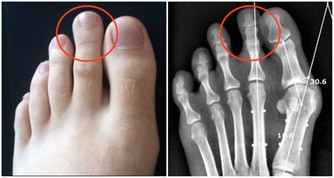

本菜多數朋友都可食用,但患痛風朋友宜少吃。